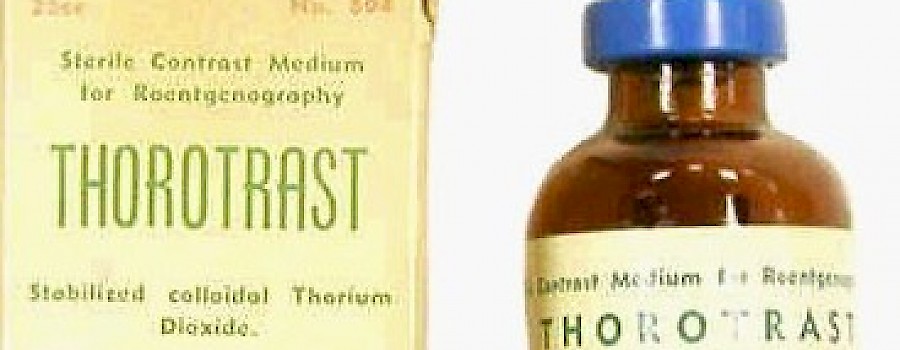

Thorotrast und Umbrathor sind die Handelsnamen für ein 1929 in den Markt eingeführtes Röntgenkontrastmittel, auf der Basis einer stabilisierten kolloidalen 25%igen Suspension von Thoriumdioxid.